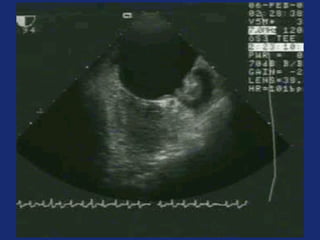

Atrial fibrillation – echocardiography

• Provides important information for initial evaluation

• Either transthoracic or transoesophageal

echocardiography may be appropriate

• Initial goal: Establish presence or absence of structural

heart disease

• Left atrial size is an important predictor of outcome

• Transoesophageal approach needed to detect thrombi or

asses left atrial apendage anatomy

Left atrial appendage